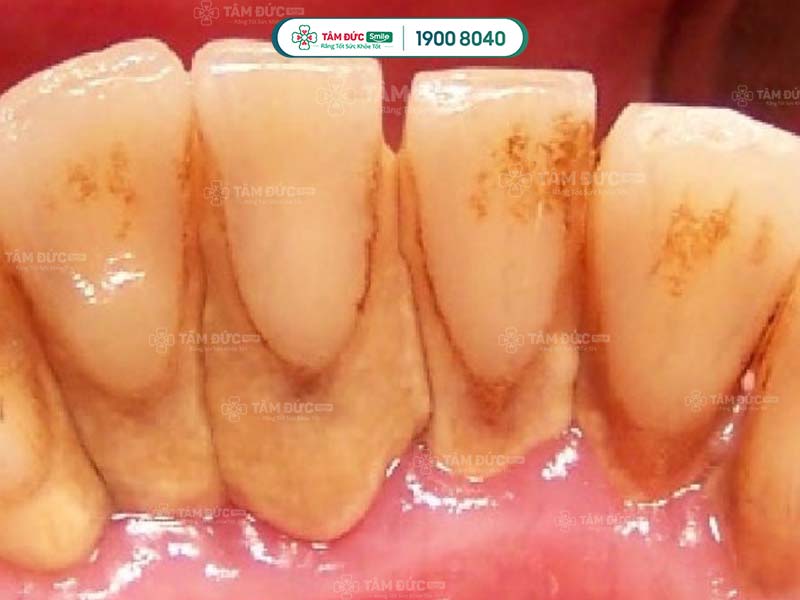

Cao răng tích tụ lâu ngày sẽ gây ra các bệnh lý như: Sâu răng, viêm nướu, tụt nướu, mòn men răng, viêm nha chu,... Do đó, cạo cao răng thường xuyên giúp Quý khách ngăn chặn vi khuẩn phát triển, giảm nguy cơ mắc phải các bệnh lý răng miệng.

Cao răng có màu sẫm, tích tụ trên thân răng làm ảnh hưởng đến thẩm mỹ nụ cười. Cạo cao răng giúp Quý khách loại bỏ các mảng bám tối màu, trả lại hàm răng trắng sáng và đẹp mắt hơn.

Vi khuẩn tích tụ trong cao răng thời gian dài sẽ tấn công vào sâu bên trong, làm hư hại răng và nướu nặng nề. Lâu dần, xương hàm của Quý khách có thể bị tiêu biến, tăng nguy cơ lung lay răng vĩnh viễn. Như vậy, cao răng nghiêm trọng có thể làm cho Quý khách đối mặt với vấn đề mất nhiều răng cùng lúc.

Để bảo vệ sức khỏe xương hàm và răng, Quý khách cần cạo cao răng định kỳ. Khi ngăn chặn được sự tích tụ của vi khuẩn, sức khỏe răng miệng của Quý khách sẽ ngày càng tiến triển tốt hơn.